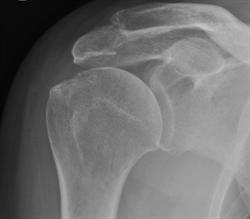

Impingement Syndrome

This is a condition in which the inner tendons of the shoulder ‘impinge’ under the bony point of the shoulder causing pain and difficulty when lifting the arm above shoulder height.

If the pain returns after the injection and physiotherapy, then a minor day-case keyhole operation may be required to give a more permanent solution. The procedure is referred to as arthroscopic sub-acromial decompression and involves a small amount of bone being shaved off the under-surface of the point of the shoulder. The Exeter Shoulder surgeons each perform around 90 of these procedures every year. Recovery from this procedure usually takes 6 to 10 weeks (click to read more about recovery).